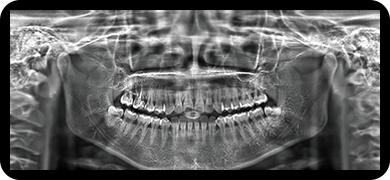

采用高性能CMOS探测器,最大FOV可达16x9cm星垂视野并支持无极可调,最小体素0.05mm。头颅采集模式,支持3s超快速扫描,最小像素99um,保证优质影像快速采集。

标配专业正畸软件

支持自动描点功能

精准定位

临床样片